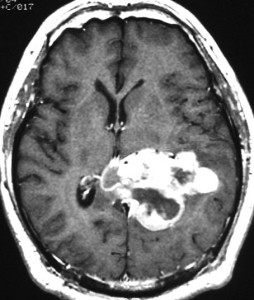

40代女性の後頭部傍矢状洞部の硬膜に発生したグレード3です。腫瘍周囲の強い浮腫のために,頭頂葉のゲルストマン症候で発症しました。術前診断は髄膜腫でしたが,腫瘍内部にのう胞(液体が溜まっている)があり,髄膜腫としては典型的な画像ではありません。右側の血管撮影にみられるように,上矢状洞が一部狭窄して腫瘍が浸潤している所見があり,腫瘍が濃染します。腫瘍の周囲の脳には出血がありました。大脳鎌と上矢状洞の壁を含めて全摘出しました。

画像と病理所見4

40代男性の大脳鎌テント接合部の硬膜に発生したグレード3です。激しい出血のために腫瘍摘出を部分摘出で中断せざるを得なかった例です。

この例でも,硬膜発生腫瘍ということは手術前の画像診断で解ってはいたのですが,髄膜腫と異なり不整な形をしてのう胞があり,一部は腫瘍壊死でした。

上の2例は,髄膜腫とは違うと一見してわかる,典型的なSFT/ヘマンジオペリサイトーマの例ですが,髄膜腫と鑑別できないようなものの方が多いです。